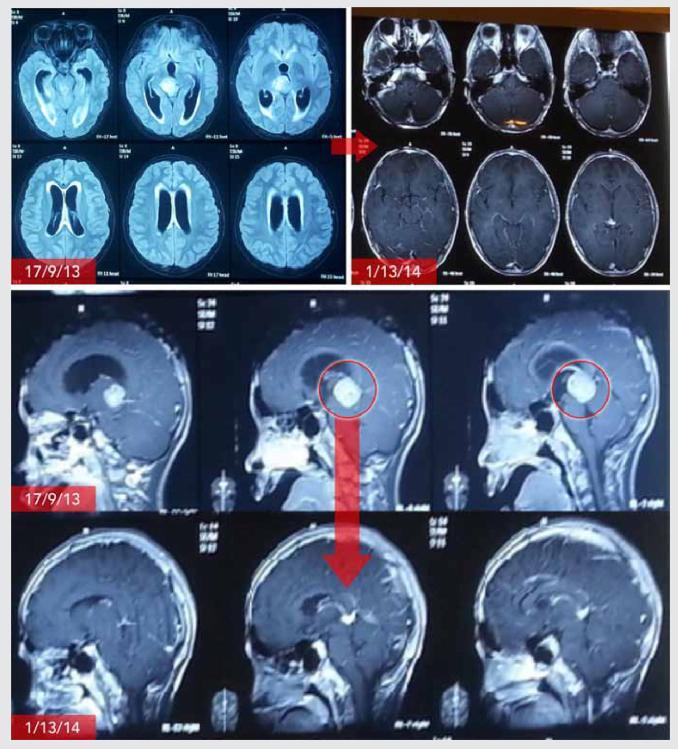

罗伯特接受电场治疗六个月后,脑部的肿瘤开始缩小,十二个月后,大部分肿瘤都消失了。